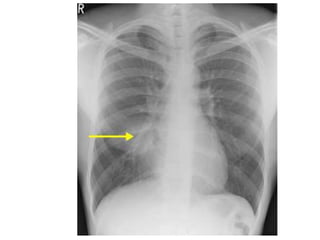

an x-ray for a patient with right middle

zone consolidation and demonstrates

air bronchograms

Silhouette sign: If the airspace adjacent to one

of the normal mediastinal or diaphragmatic

contours is filled with dense material i.e.

consolidated, then the normal air-soft tissue

interface is lost and the normally seen edge of

the silhouette disappears

.